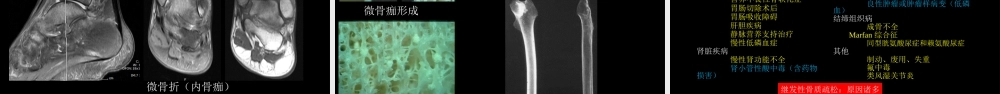

影像诊断学习与扩展:代谢性骨病中国石油中心医院影像科杨景震2016病例交流(23)(有三部分内容)先看这些图,是肿瘤吗??临床病例一吴某某,男,52岁。缘于2年前(2014年4月)因运动不慎致右侧髋部扭伤,随即出现右侧髋部疼痛,伴右下肢体活动受限,无腰背部疼痛,休息后可缓解。同年10月行走时不慎右侧髋部再次扭伤致疼痛再发,进行性加重,就诊当地中医院,诊断不详,口服中药汤剂治疗2个月,症状缓解。2015年4月长时间行走(持续行走4公里左右)后右髋部疼痛再发,就诊上海市第六医院,行髋关节MRI、CT等检查,未见骨折征象,考虑关节滑膜炎,口服西乐葆对症治疗,症状缓解。此后上述症状反复发作,多于劳累后加重,服用西乐葆后症状缓解。8个月前,右侧髋部疼痛再次加重,伴活动明显受限,就诊上海长海医院,查骨ECT示全身多发骨转移瘤。PET-CT示:C7棘突、两侧多根肋骨骨折,两侧股骨头颈交界处炎症可能。10余天前患者右侧髋部疼痛再次加重,伴右侧胁肋部疼痛,与呼吸活动无明显相关。也曾经就诊北京积水潭医院。现为求进一步诊治入北京空军总医院(由于各方面体征和表现不典型,也不确定选择适合的住院学科,故暂住肾病科)。该病例源自北京空军总医院熊明辉教授内容一:入院后查体:1.胸廓挤压试验(+),双侧髋关节叩痛,双侧髋关节活动内旋外展受限,双侧4字试验(+),骨盆分离试验(+),其余关节无压痛。考虑不能排除脊柱关节病可能。主要排除强直性脊柱炎、银屑病关节炎、肠炎型关节病、瑞特综合症等疾病。血沉6mm、HLA-B27阴性,类风湿因子<20.0IU/ml,排除强脊炎。2.既往髋关节CT、MRI重新阅片,见骨皮质变薄、稀疏、密度减低,骨小梁增粗排列紊乱,提示骨代谢异常。查电解质:血钙磷正常范围。尿钙6.84mmol/24h、尿磷13.68mmol/24h↓。全段甲状旁腺激素3.05pmol/L。3.入院检查:乙肝两对半:乙肝肝炎E抗体0.01阳性+S/CO↑、乙型肝炎表面抗原31.02阳性+IU/mL↑、乙型肝炎核心总抗体8.03阳性+S/CO↑。梅毒抗体:梅毒血清特异性抗体27.93阳性+S/CO↑。补体C30.592g/L↓、补体C40.0906g/L↓。(1)补体降低,提示存在免疫反应,给予抗核抗体+抗核抗体谱检查,结果阴性,排除系统性红斑狼疮。(2)患者为小三阳,ALT升高,前白蛋白降低,乙型肝炎病毒核糖核酸定量<500copy/ml;感染科会诊后指出:既往有肝炎病史,2009年开始口服阿德福韦酯1片1/日抗病毒治疗。(3)梅毒特异性抗体实验阳性,给予快速梅毒血清反应素试验,RPR滴度试验...